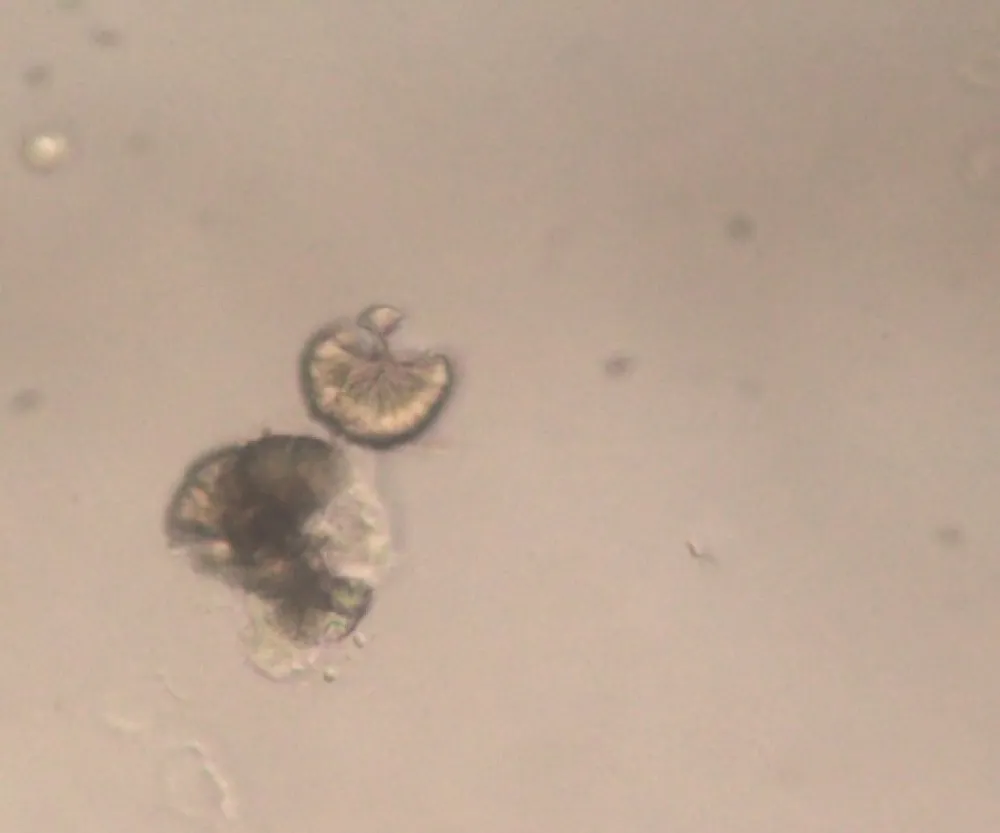

Uma causa incomum de hematúria glomerular intermitente!

Uma causa incomum de hematúria glomerular intermitente!

Hematúria pós infecção, caso clínicos para auxiliar no entendimento de causas glomerulares comuns e raras...